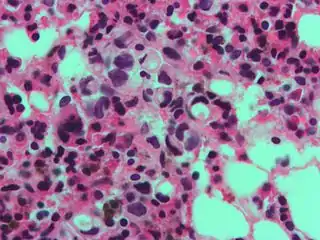

The name of the cell comes from its appearance; signet ring cells resemble signet rings. They contain a large amount of mucin, which pushes the nucleus to the cell periphery. The pool of mucin in a signet ring cell mimics the appearance of a finger hole and the nucleus mimics the appearance of the face of the ring in profile.

A signet ring-like foamy macrophage, which may mimic a cancer cell, but the texture of the nucleus is similar to that of a normal macrophage.

High magnification micrograph showing signet ring cells, with clear cytoplasm, in metastatic breast carcinoma. H&E stain.